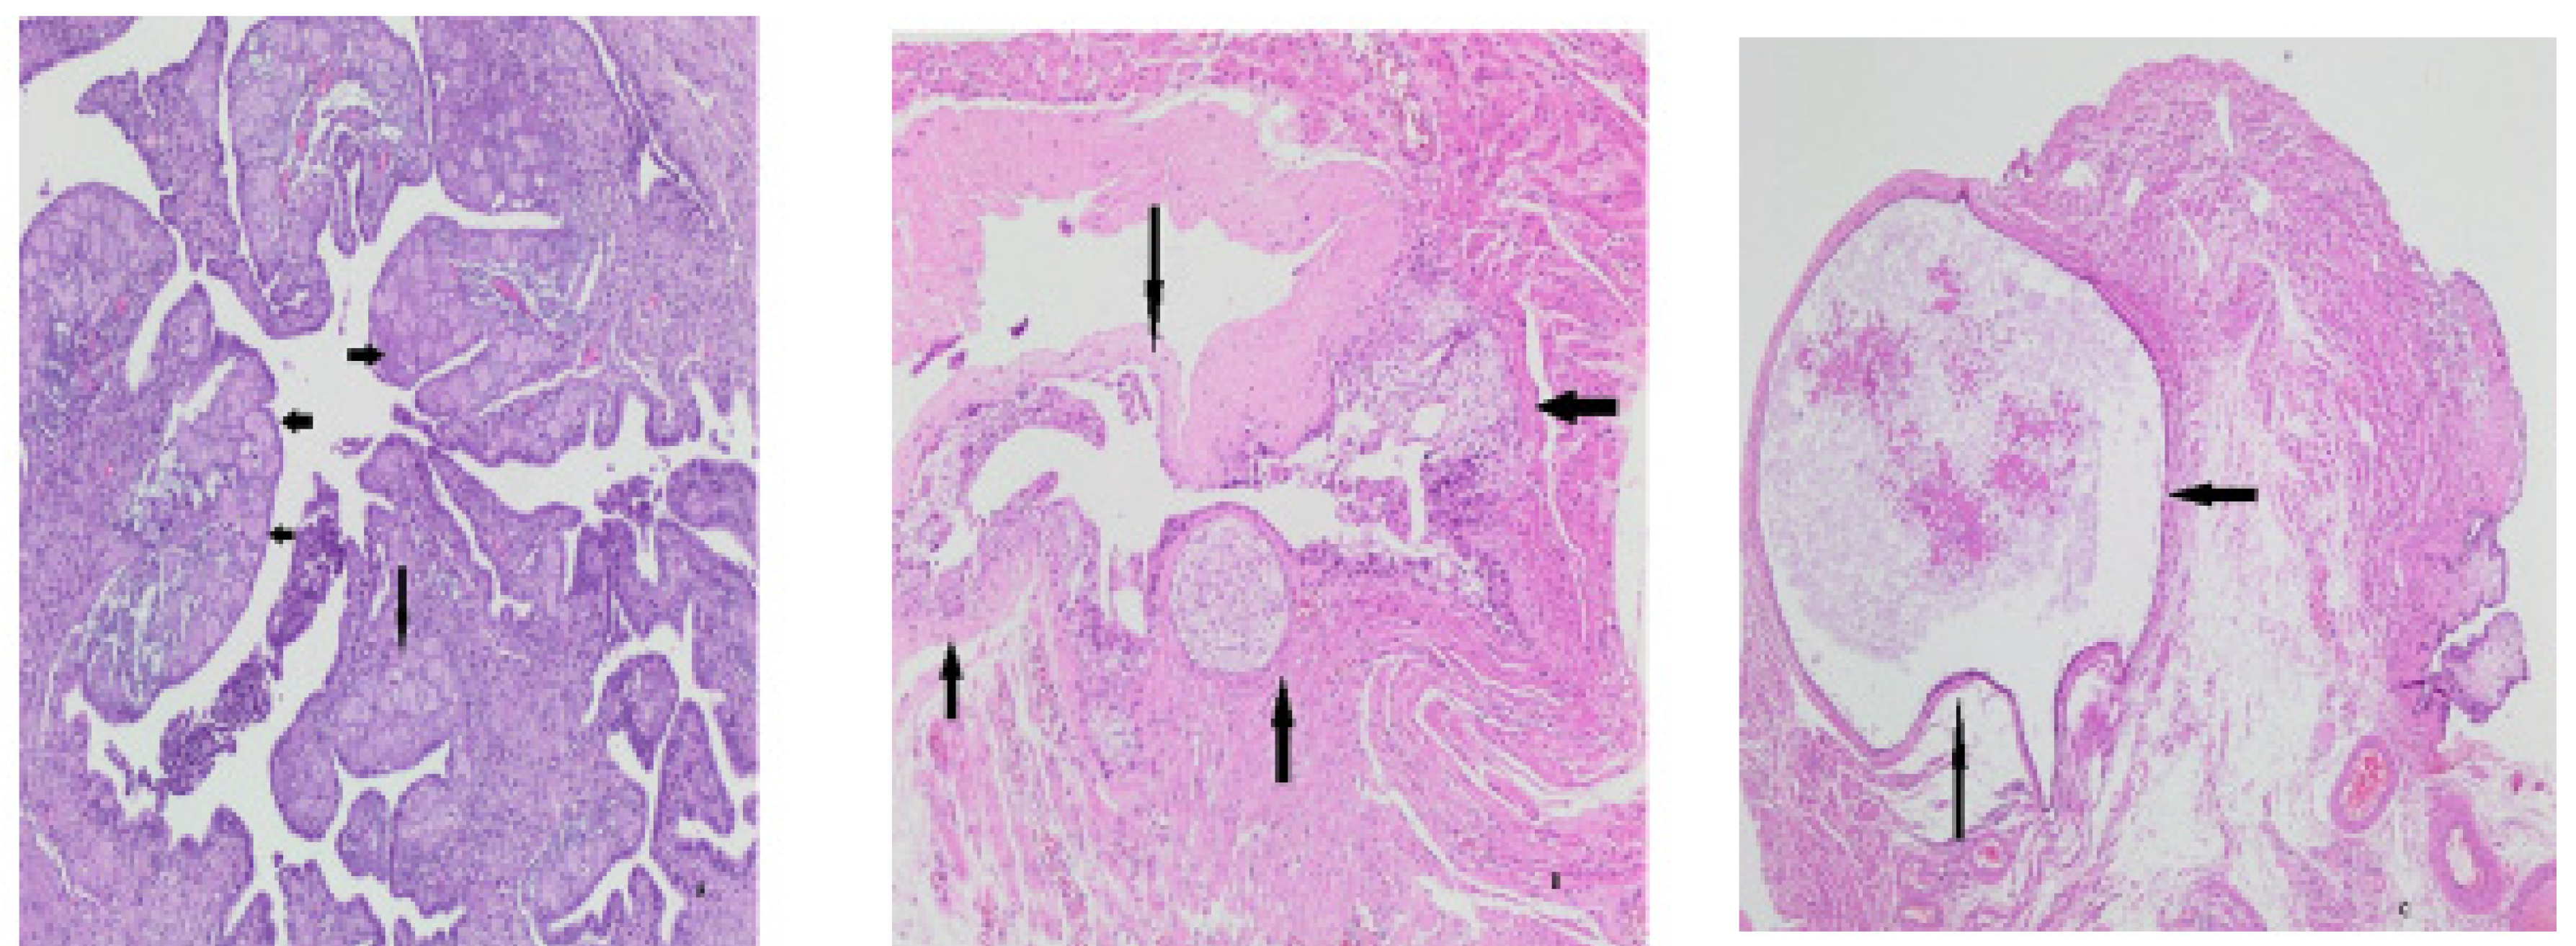

Figure 4. Extra findings. Decidua (arrows) in tubal tissue (A), Walthard remnants (arrows) (B), paratubal cyst (arrows) (C).

Higher scoring with KI-67 in those with fewer gravities and parities, p=0.016 and p=0.049, respectively. There was no correlation with age (p>0.05) (Figure 3). No correlation was found between Tufting, SCOUT, p53 signature, atypia, intraepithelial lymphocyte and infiltration findings, and age, gravity, and parity (p>0.05) (Figure 3). Additional pathologic findings were paratubal cyst in 10 cases (7.24%), decidua in 4 cases (2.89%), Walthard nest in 5 cases (3.62%), paratubal cyst with Walthard nest in 2 cases (1.44%) and endometriosis and calcification in one case (0.72%) (Figure 4)